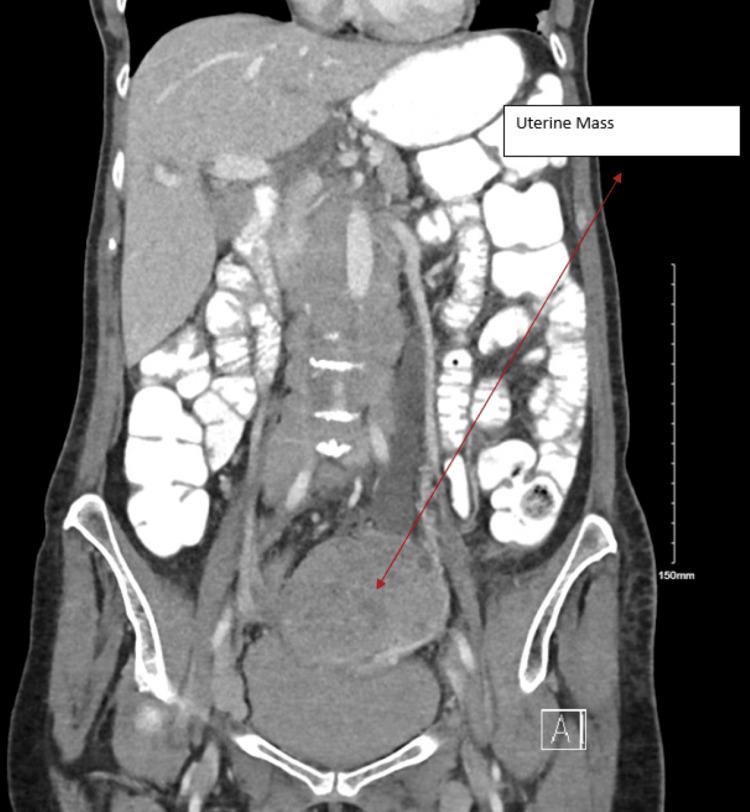

https://cdn.ncbi.nlm.nih.gov/pmc/blobs/cb94/10980271/1b804e947499/cureus-0016-00000055153-i01.jpg